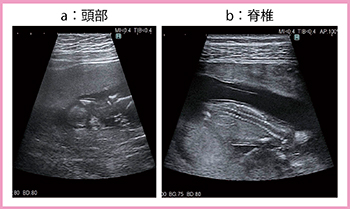

2.プローブの進化

高周波であるリニアプローブは,コンベックスプローブよりも高解像度であるものの,深部を広角で観察できないため,通常,表在領域の血管や乳腺,甲状腺,関節の撮像に用いられてる。しかし,最近では,リニアプローブでも扇形の広角視野が得られるトラペゾイドスキャンが可能となり,産婦人科領域でも使用されるようになった。トラペゾイドスキャンでは走査密度が若干広がるため,深部での方位分解能(左右方向)が通常の撮像よりもやや劣るが,コンベックスプローブよりは高解像度である。

さらに,ARIETTA 850の新しいリニアプローブ「4G CMUT」は,半導体加工技術を応用し,音響整合層が不要なため,きわめて高解像度な画像が得られる。図2に示すとおり,胎児の頭蓋骨縫合がわずかに確認できる(a)ほか,妊娠初期の胎児の脊椎の画像(b)からは,近年報告されている妊娠10〜12週での髄膜瘤や脊椎破裂の診断も可能であるとの印象を持った。

図2 4G CMUT(トラペゾイドスキャン)による胎児の画像